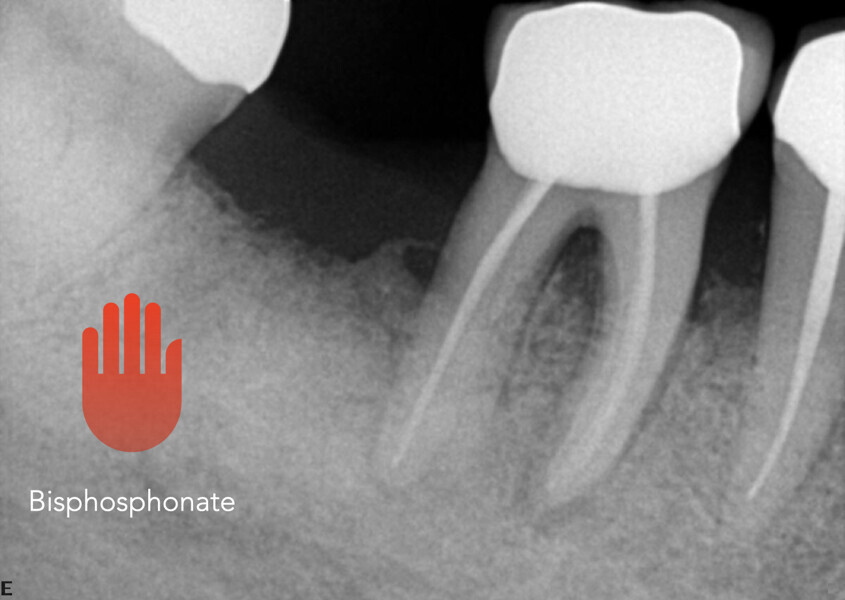

Bisphosphonates, when administered intravenously for the treatment of cancer, have been associated with osteonecrosis of the jaw. The mandible is twice as frequently affected as the maxilla, and most cases occur after high-dose intravenous administration used for some cancer patients. “Phossy jaw” has been described since Victorian times. Imaging findings related to bisphosphonate-related osteonecrosis of the jaw include osteolysis, osteosclerosis, cortical bone erosion, formation of sequestra, persistent alveolar socket after tooth extraction, periosteal neoformation, widening of the periodontal ligament, periradicular radiolucencies, thickening of the lamina dura and of the cortex, and narrowing of the mandibular canal.

Some 60% of cases are preceded by a dental surgical procedure that involves the bone, and it has been suggested that bisphosphonate treatment should be postponed until after any dental work to eliminate potential sites of infection. The use of antibiotics may otherwise be indicated prior to any surgery. In both cases described here, bisphosphonate-related osteonecrosis of the jaw was not triggered by a surgical procedure but by chronic apical infection. It is thus important that all patients who are to undergo bisphosphonate treatment have a CBCT scan taken, not just a panoramic and periapica radiographs, because these cannot show hidden infections.